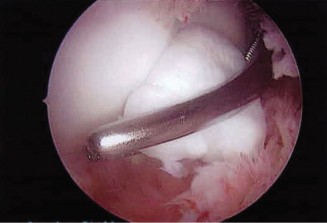

The correct answer is (A). In a young patient, the most likely injury associated with a glenohumeral dislocation is a labral tear (see Fig. 2–31). In an older patient, >40 years old, a rotator cuff tear is more likely. Other possible associated injuries include:

Figure 2–31 MRA demonstrating an anterior labral tear.